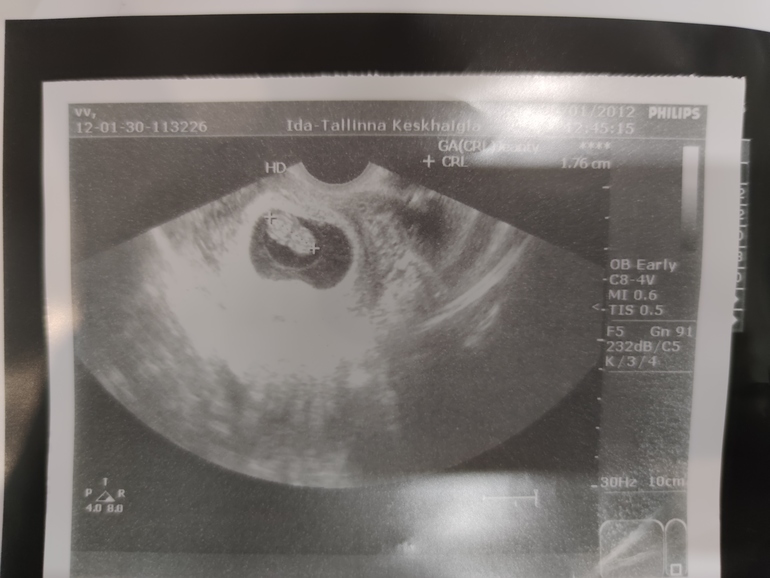

Сходила на узи. Нашли креветку)

Услышала сердцебиение, слёзы сами полились градом 😭 Спустившись вниз, меня ждал мой сынок. Будущий старший брат...Как-то только сейчас начинаю это принимать и осознавать в полной мере.

КТР 4.1 мм, срок по узи рисуется 6 недель 1 день, ПДР исходя из этого на 24.06.2021. По хгч примерно так и прикидывала) Расхождение с месячными больше 2 недель конечно.

Кстати, что там метод Рамзи говорит? Мальчики слева, девочки справа, или наоборот? 🤣

это мой младший сын :)